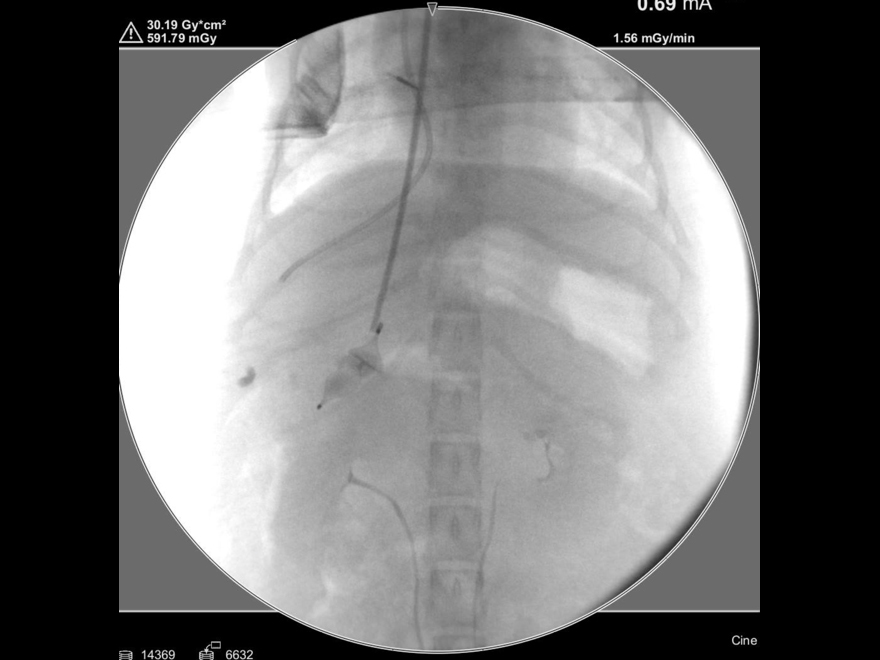

手術中の様子:セルジンガー法

手術中の様子:カテーテル設置後

手術中の様子